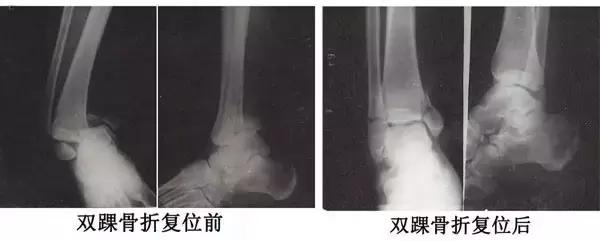

国际医疗部康复理疗科专家张林运用“闭合性手法复位”为患者治疗前后的X光片:

一、双踝骨折